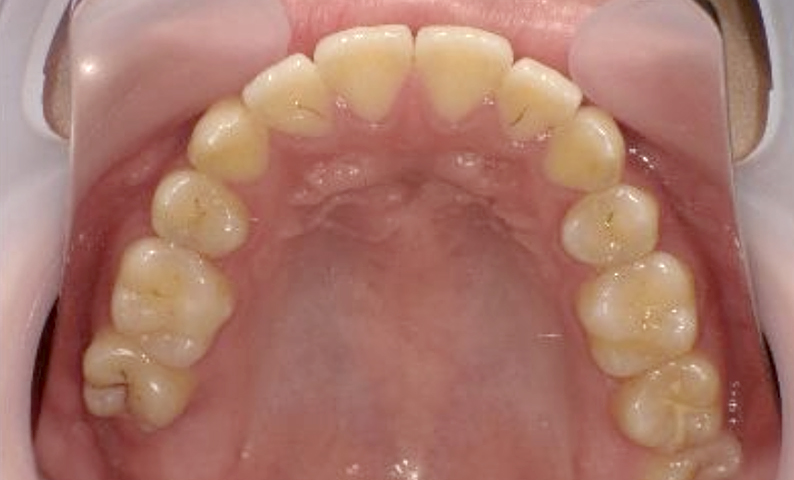

症例_004 上下顎の部分矯正

治療期間:8ヶ月金額:54万円+税女性前歯のガタガタ捻転歯

| Before | After |

|---|---|

|